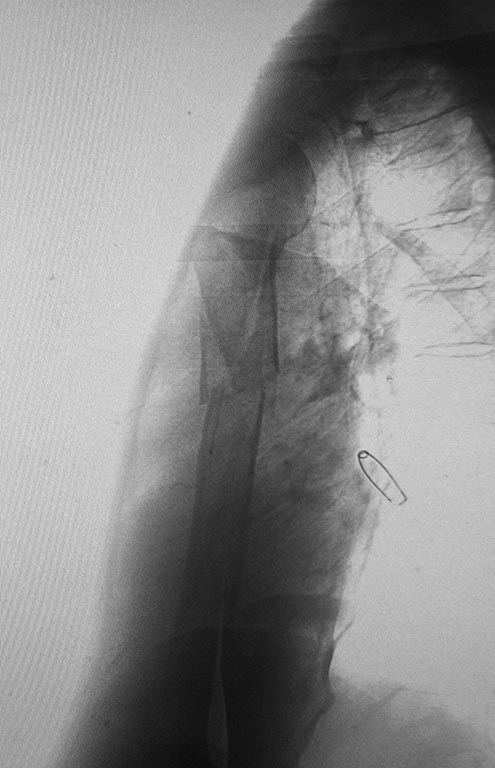

[Ortho] Перелом плечевой кости